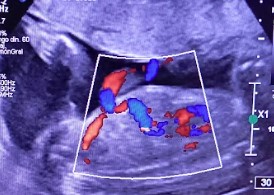

Se presenta el caso de una paciente de 23 años de edad, secundigesta, sin antecedentes personales ni familiares de relevancia. La paciente adjunta el estudio de screening de aneuploidías de la semana 11-14, que arroja bajo riesgo. Las imágenes 1 y 2 describen los hallazgos identificados durante la evaluación de la anatomía fetal en la semana 12. Las imágenes 3, 4 y 5 corresponden a los controles ecográficos posteriores, del segundo y tercer trimestre. La imagen 6 muestra al recién nacido. Seleccione la opción correcta: A. Corresponde a una hernia umbilical fisiológica con resolución más tardía. B. Corresponde a una gastrosquisis con cierre espontáneo intraútero. C. Corresponde a un onfalocele con ruptura del mismo. D. El defecto de pared cerró espontáneamente mejorando el pronóstico y riesgo de complicaciones gastrointestinales. Figura 1: se visualiza corte axial del abdomen fetal, a nivel de la inserción del cordón umbilical, con Doppler color en semana 12. Figura 2: se observa corte axial, a nivel de la inserción del cordón umbilical en la pared abdominal anterior, en semana 12. Figura 3: corte sagital a nivel de la inserción del cordón en la pared abdominal anterior, con Doppler color, en semana 20. Figura 4: corte axial del abdomen fetal, en semana 32, donde se identifica dilatación de las asas intestinales. Figura 5: corte axial del abdomen fetal, en semana 32, donde se identifica dilatación de las asas intestinales, con la utilización del Doppler color. Figura 6: se observa al recién nacido.

El caso presentado corresponde a una paciente de 23 años, secundigesta, sin antecedentes personales de relevancia, con embarazo único y espontáneo, que concurre al consultorio de ecografía para realizar un screening combinado del primer trimestre en la semana 12. Se evidencia solución de continuidad en la pared abdominal anterior, adyacente al cordón umbilical, con exteriorización de asas intestinales, compatible con gastrosquisis (Figuras 1 y 2).